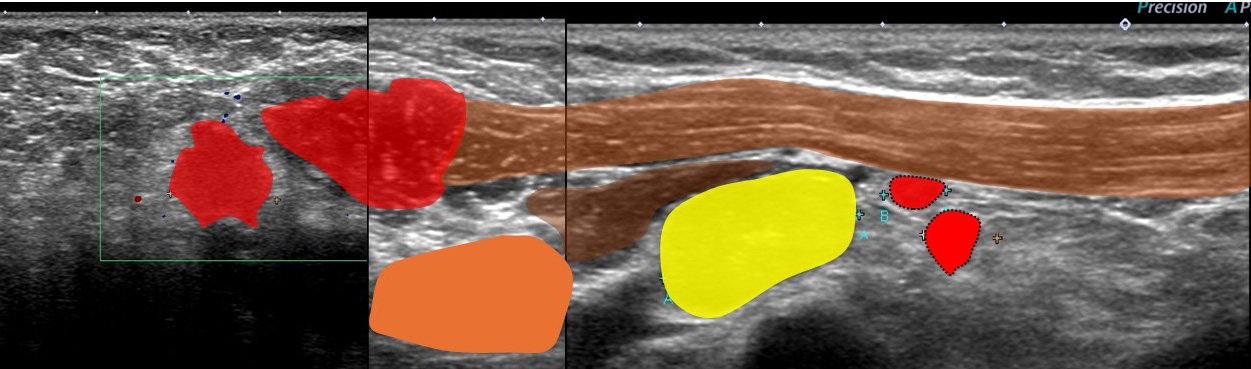

レベル2リンパ節 これが一番大きい 2㎝

形はリンパ節の形をしており「節外」では(画像上)なさそう。

大きなレベルⅡは、レベルⅢに近い部位までせり出し、その奥(図中央)にはレベルⅢが

確認できる。

←外側 (皮膚側) 内側(奥)→

これらエコーをつなぎ合わせたもの

リンパ節は黄色に表現

大胸筋(茶色)の裏に小胸筋(こげ茶色)

大胸筋の外側にリンパ節2つ、大胸筋の裏にリンパ節1個 これら3個がレベルⅠ

小胸筋裏にリンパ節(これが最大で2㎝)これがレベルⅡ

それより内側(奥)に比較的小さいリンパ節2個 これらがレベルⅢ

色分けすると 赤とオレンジ:レベルⅠ、 黄色:レベルⅡ 、赤(周囲に点線の小さいもの):レベルⅢ